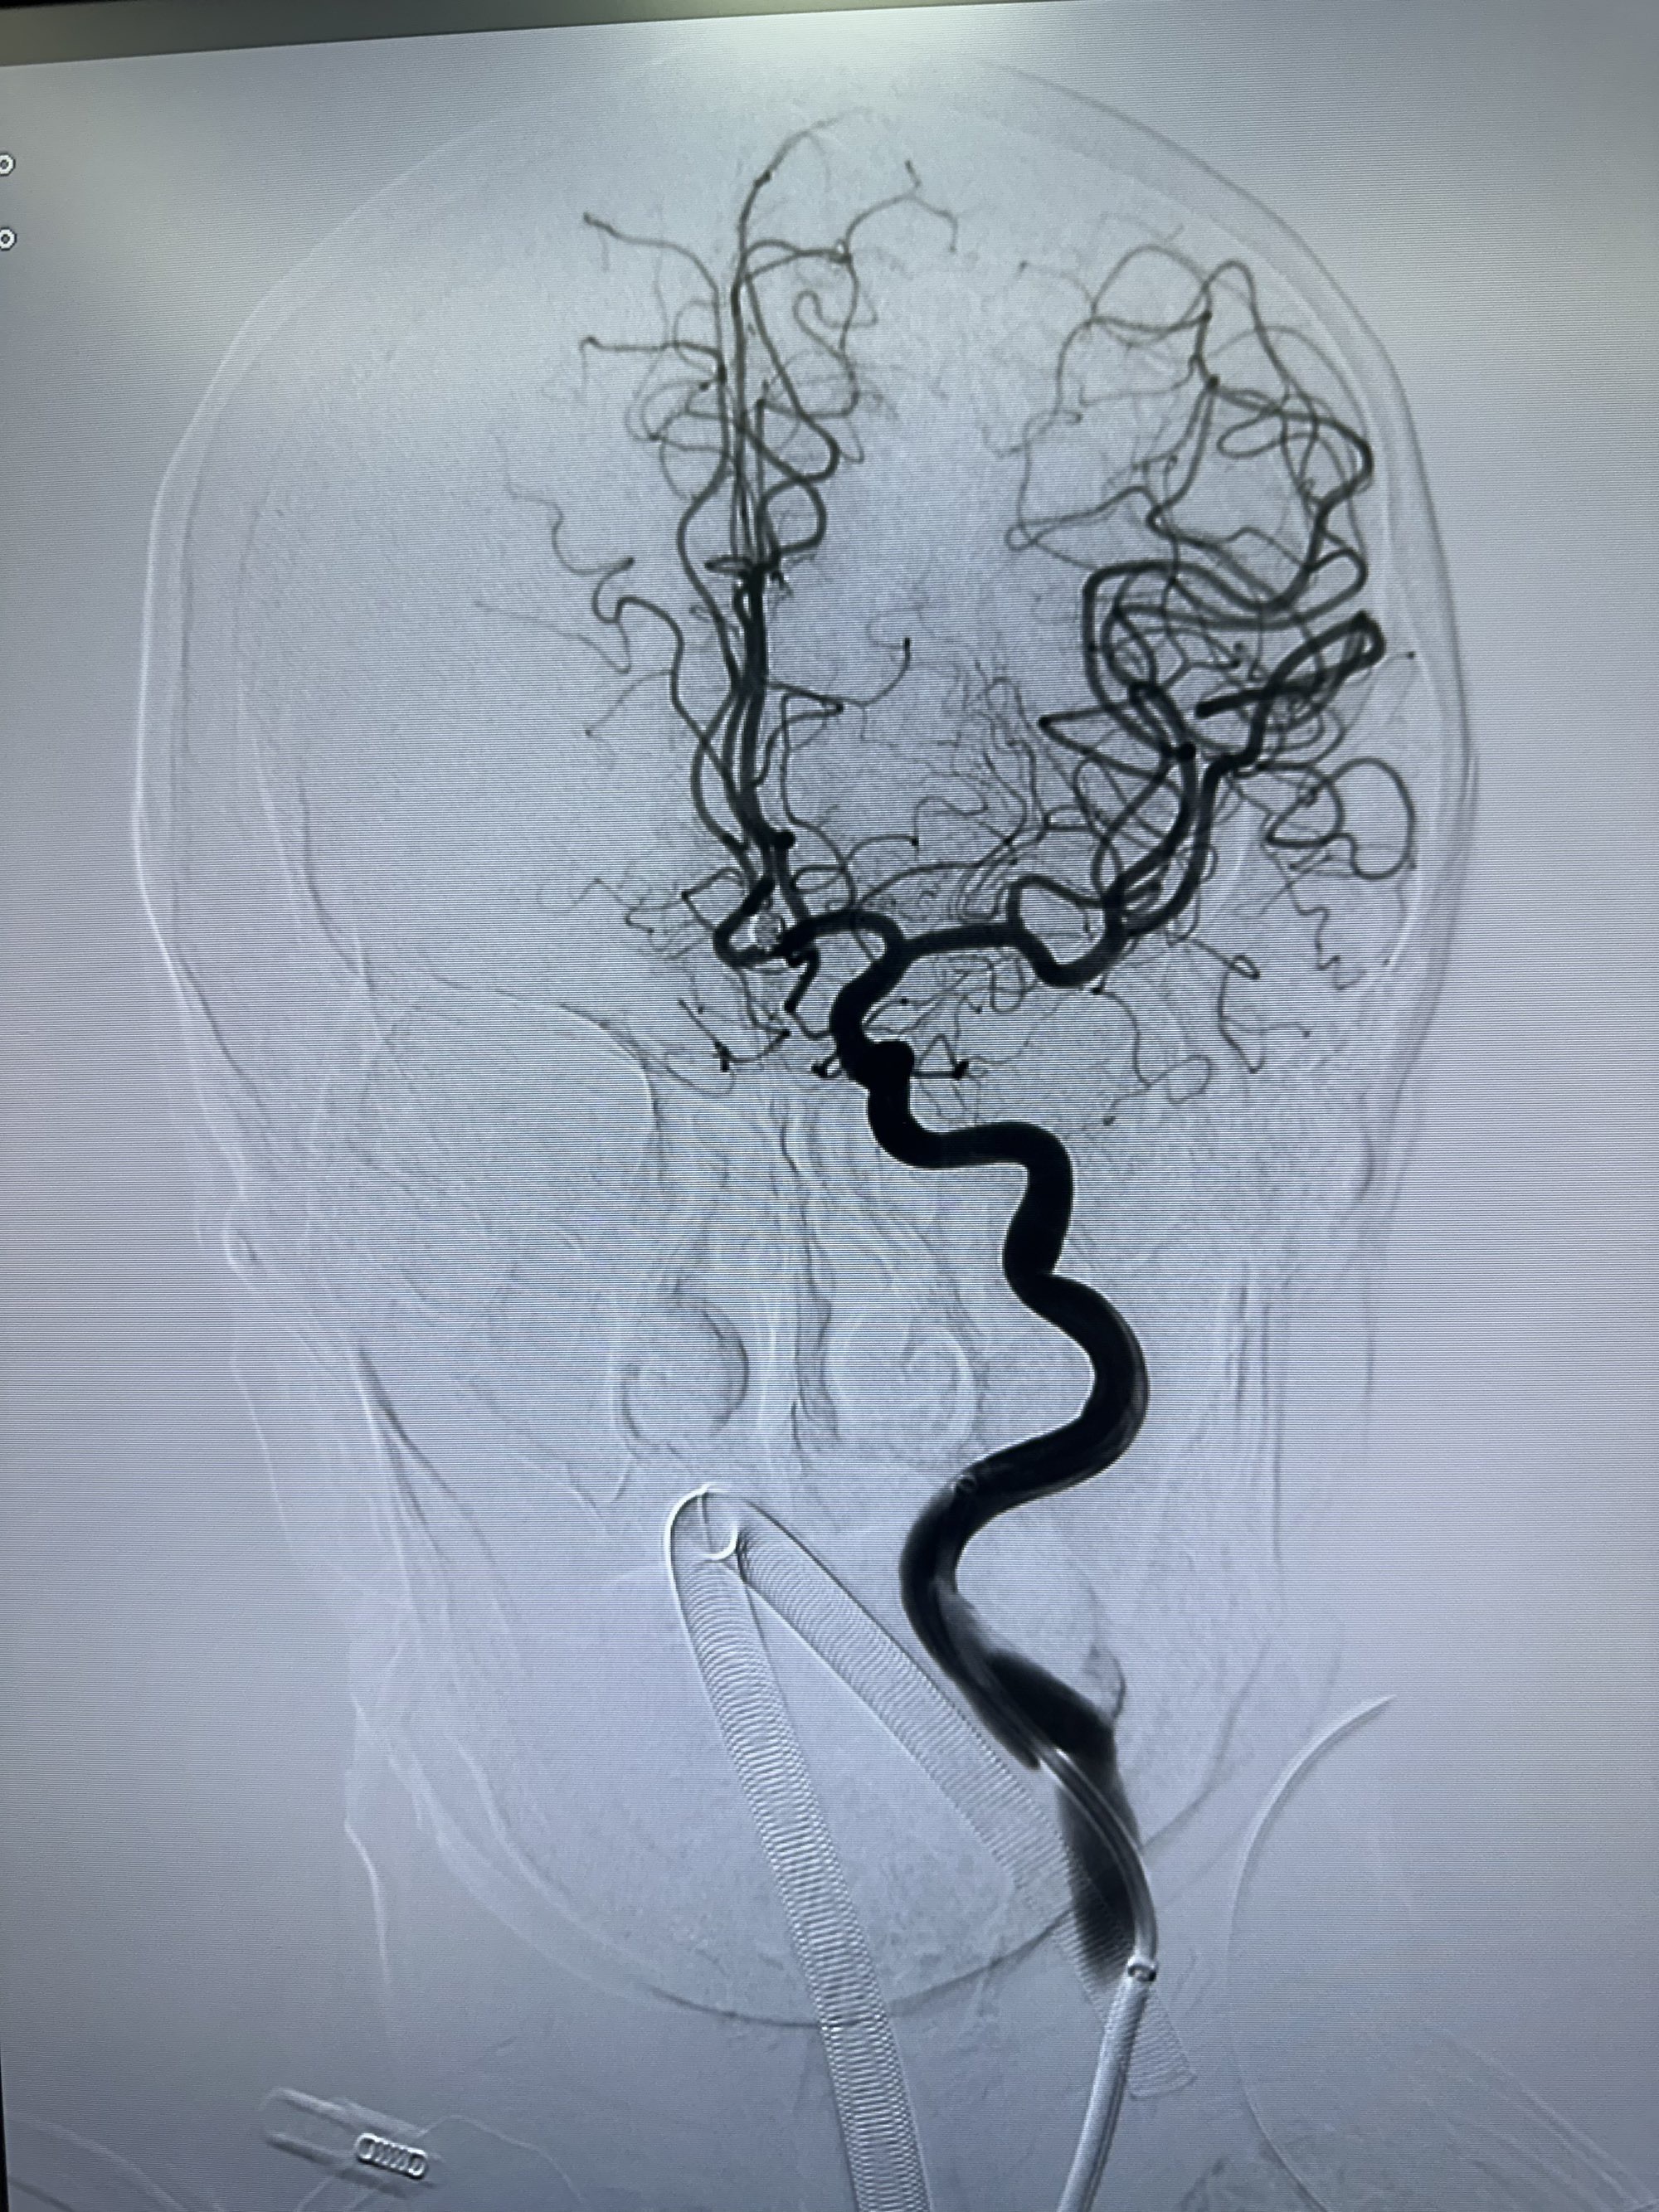

正位

骨窗

侧位